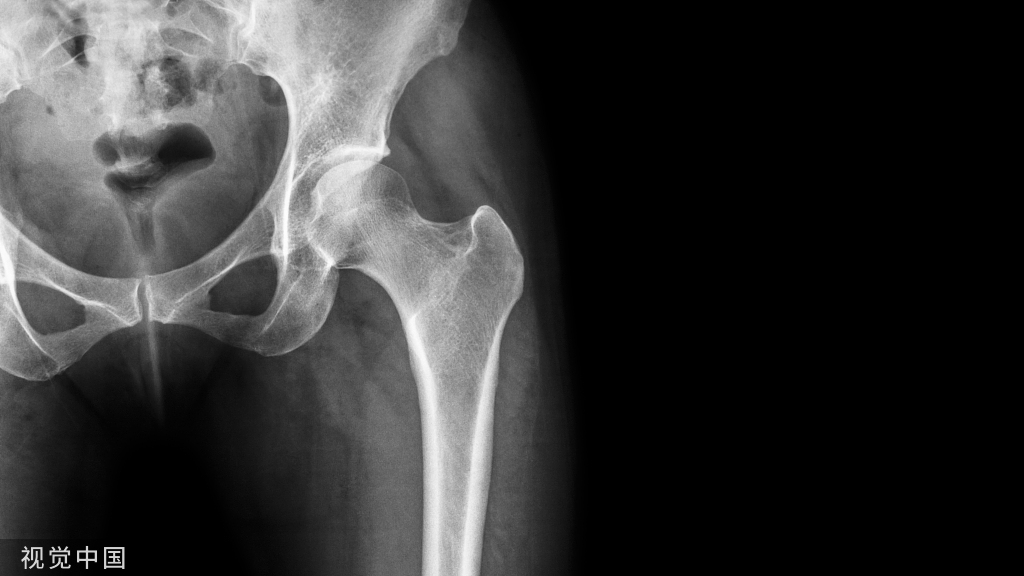

MSU结晶可以沉积于脊柱的任何部位,例如关节突关节、黄韧带、硬膜外间隙(椎管内)、椎弓根、椎板、椎间盘等。但是由于关节突关节局部的氢离子浓度较高,酸性环境有利于MSU结晶沉积,因此先累及关节突关节继而发生骨质破坏,最后韧带等部位才会受累。痛风石沉积到关节突关节可以导致其发生穿凿样改变及斑片状破坏,降低脊柱后柱稳定性,从而导致椎体滑脱。此外,累及寰枢关节时也可发生病理性骨折或者压迫延髓导致急性呼吸衰竭。椎板骨质附近MSU结晶长时间沉积可以造成继发性椎管狭窄,CT上容易与黄韧带钙化所致的椎管狭窄相混淆。痛风石不仅可以在椎管占位造成继发性椎管狭窄,有时急性发作后压迫脊髓也可以导致瘫痪。这是由于MSU结晶的机械性和化学性作用刺激周围软组织,从而使痛风石肿胀,局部组织水肿坏死,迅速地对脊髓造成压迫。

痛风石造成的节段不稳、压迫、炎症反应三者互相作用,是病情突然恶化的主要原因。文献中也有报道痛风石压迫脊神经造成腰痛伴左下肢感觉功能障碍的情况,这需要与腰椎间盘突出相鉴别。痛风一般不会侵犯椎间盘,但是近些年也有报道痛风累及颈椎间盘及邻近椎体终板的病例,影像学误诊为感染性椎间盘炎。当出现低热的症状,则更需要与感染性疾病相鉴别。脊柱痛风不同于外周关节的痛风。外周关节的痛风石在体表容易触及,急性期发作时还会有红肿热痛及关节活动障碍的临床表现。而脊柱痛风位置较深,体表难以触及,且病程发展缓慢,一般不会产生临床症状。多以神经根受压引起特定节段的感觉或运动功能障碍为首发临床表现,L4~S1节段最常受累,可能与该处脊柱负重较大、活动度较高、退行性病变最容易发生有关。当痛风石累及到椎管时,绝大部分患者跖趾关节、踝、膝关节或多或少都会有痛风石沉积。因此有外周关节痛风史且血尿酸水平异常者出现以上症状时需要与腰椎间盘突出、腰椎椎管狭窄等疾病鉴别。

痛风石在MRI上表现为均匀一致的图像,T1、T2的信号范围从中到低,不易与其他骨性成分相区别,不过当使用对比剂钆时,周边会出现均匀或不均匀的对比剂增强图像,这提示有反应性血管的生成,同时表明脊柱痛风可能会导致一些血管化的物质产生。相比来说,CT对于脊柱椎管痛风的诊断优于MRI,累及椎小关节的患者可出现关节突关节边界清晰的囊性穿凿样改变,还可见关节侵蚀和硬化边缘等改变。但是CT和MRI对于MSU结晶均无特异性。最近,双源CT双能量成像技术(DECT)的出现对于脊柱痛风的诊断带来了极大的便捷,它的工作原理主要是以原子数衰减为基础,由于钙的原子数要比尿酸盐高,在衰减上有更大的能量变化,该能量衰减上的差异通过计算机直接转化为不同的ct值,最终在双能量后处理图像上显示为绿色荧光标记的尿酸盐和紫色荧光标记的钙离子(骨性结构)。由此可以清楚显示MSU结晶的沉积的部位、大小和形状。但是DECT的检出率受BMI值、既往最高尿酸值、痛风病程的影响,而且由于成本高、辐射剂量大、噪音大等缺点,目前未在临床上得到广泛应用。